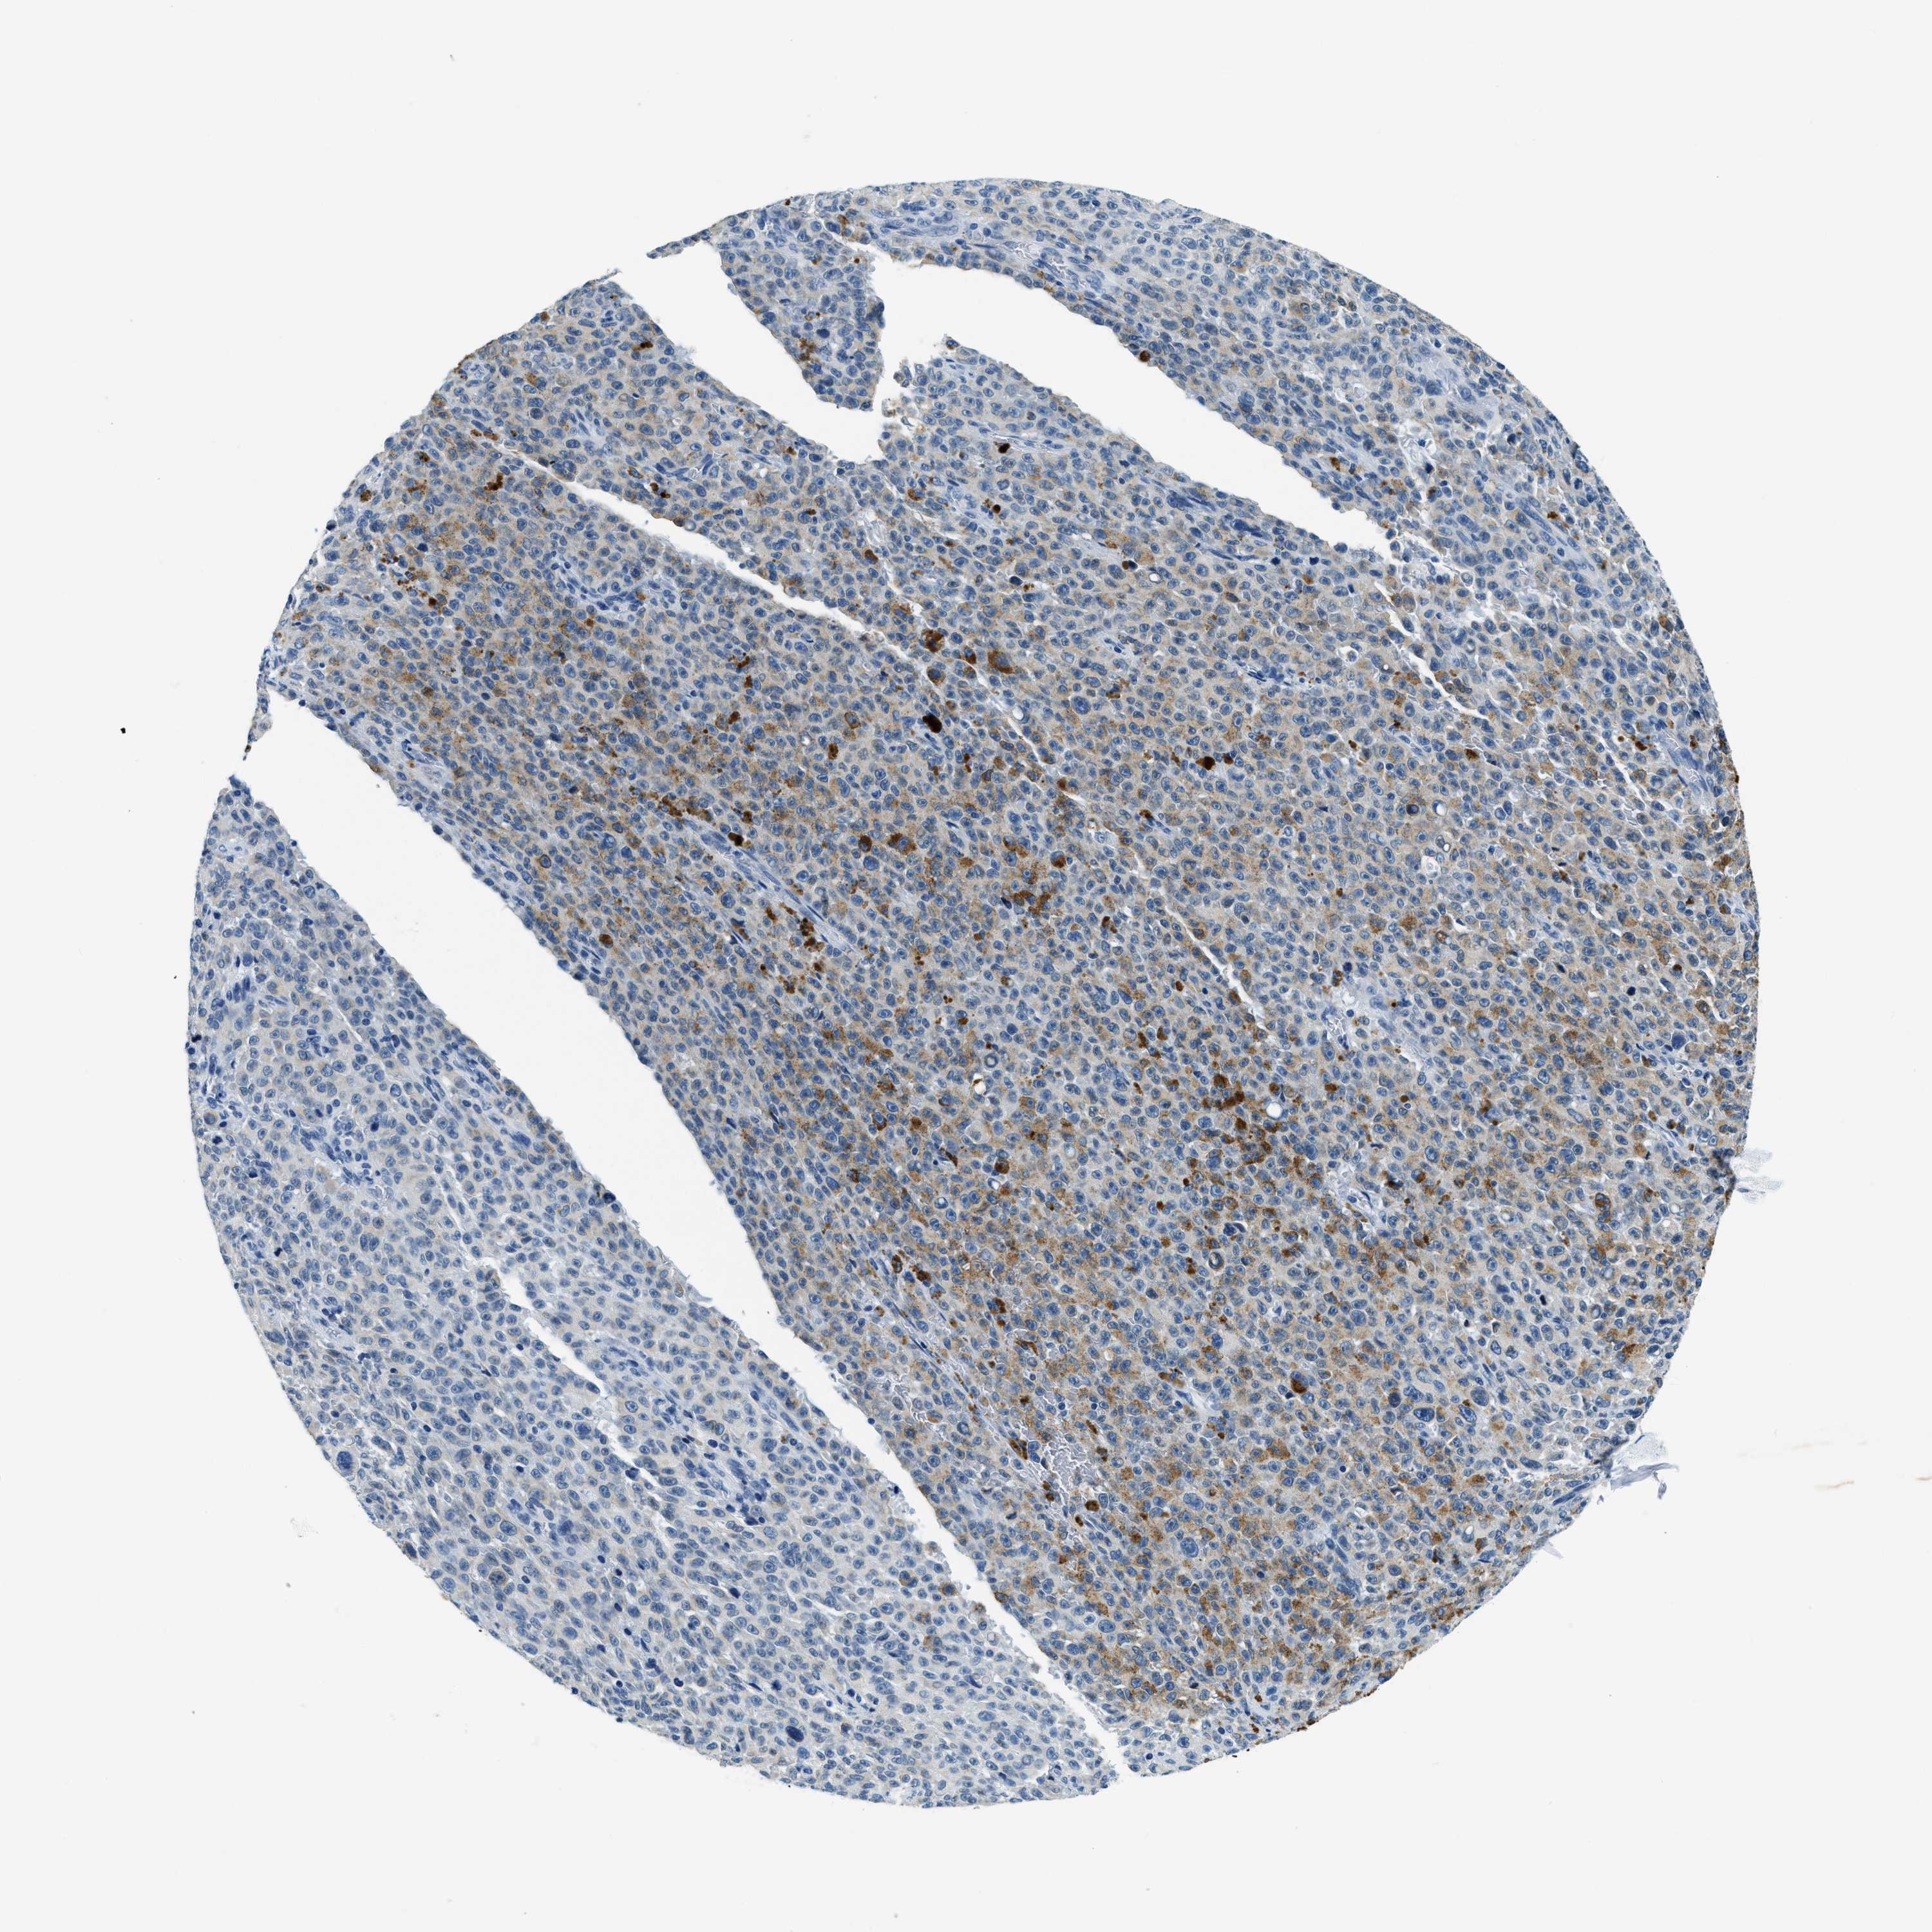

MELANOMA - Protein expressioni

A mouse-over function shows sample information and annotation data. Click on an image to view it in a full screen mode. Samples can be filtered based on level of antibody staining by selecting one or several of the following categories: high, medium, low and not detected. The assay and annotation is described here.

Note that samples used for immunohistochemistry by the Human Protein Atlas do not correspond to samples in the TCGA dataset.

Antibody stainingi

Antibody staining in the annotated cell types in the current human tissue is reported as not detected, low, medium, or high, based on conventional immunohistochemistry profiling in selected tissues. This score is based on the combination of the staining intensity and fraction of stained cells.

Each image is clickable and will lead to virtual microscopy that enables deeper exploration of all samples and also displays staining intensity scores, fraction scores and subcellular localization as well as patient and tissue information for each sample.

Antibody HPA013448

Staining

High

Medium

Low

Not detected

Intensity

Strong

Moderate

Weak

Negative

Quantity

>75%

75%-25%

<25%

None

Location

Nuclear

Cytoplasmic/membranous

Cytoplasmic/membranous,nuclear

Malignant melanoma, NOS

Malignant melanoma, Metastatic site